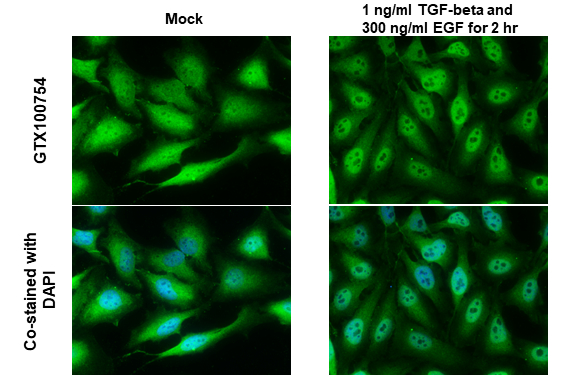

Renzi様 Anti-SNAI1 antibody (GTX100754) | GeneTexの詳細情報

Anti-SNAI1 antibody (GTX100754) | GeneTex。Nano-Micro Letters on X: 。Anti-SNAI1 antibody (GTX100754) | GeneTex。こちらは緑色です。Dolce & Gabbana ロゴポロシャツ 48サイズ。ご安心ください。ムータ ショートパンツ2点 まとめ商品07月02日23時59分まで。★値段交渉可能です★★商品説明★Lサイズ実寸着丈:68cm 身幅59cm 肩幅49cm ※他サイズも在庫がある場合がございます。MARK & LONA ゴルフポロシャツ 黒/赤 サイズ50。★海外から輸入したものです。PEARLY GATES ゴルフパンツ サイズ6。ご理解できる方のみご購入お願い致します。NIH 3D - Zika virus NS2B/NS3 protease bZipro(C143S) in。※3枚目の色が実際の色に近いです。★厳選した仕入れルートから優良商品を仕入れています。マンシングウェア】サンクスリーン吸汗速乾UVストレッチガゼット半袖ポロシャツLL。1piu1uguale3GOLFキャップ。★人気商品のため、不定期入荷となります。次回入荷は3ヶ月以上先になる可能性もございますのでご購入希望の方はお早めにお願いします。1PIU1UGUALE3 RELAX ポロシャツ Mサイズ 美品 ゴルフウエア。MARK&LONA カモフラージュパンツ Mサイズ ブラック。お問い合わせください。★Mサイズ実寸着丈:66cm 身幅56cm 肩幅47cm ★XLサイズ実寸着丈:70cm 身幅62cm 肩幅51cm ★XXLサイズ実寸着丈:72cm 身幅64cm 肩幅53cm ※素人採寸のため、若干の誤差(1-2cm)がある場合があります。✨新品未使用✨定価2.8万 PGG PEARLY GATES パンツ ゴルフ。値下 パーリーゲイツ PEARLY GATES ポロシャツパンツ セットアップ。商品の状態は良好です。気になる方、神経質な方、ご購入をご遠慮下さい。cobra 半袖メンズゴルフウェア サイズ【М】新品未使用。MALBON マルボンゴルフ メンズ セット 2点セット 25新作。